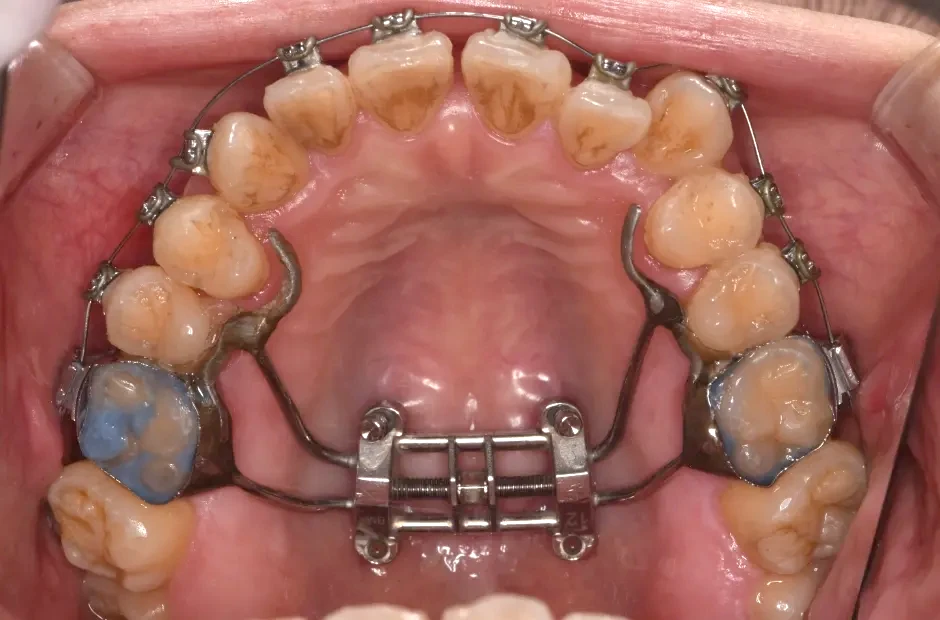

ゆがみ(左右非対称)

| 診断名・主訴 | ゆがみ(左右非対称) |

|---|---|

| 年齢・性別 | 20歳・女性 |

| 治療期間・回数 | 2年半 30回 |

| 治療に用いた主な装置 | 急速拡大 アンカー |

| 抜歯部位 | 左右上5番 |

| 治療費 | 70万円(税抜) |

| リスク・副作用 | 装置による違和感・疼痛・歯肉退縮・歯根吸収・虫歯のリスクなど |